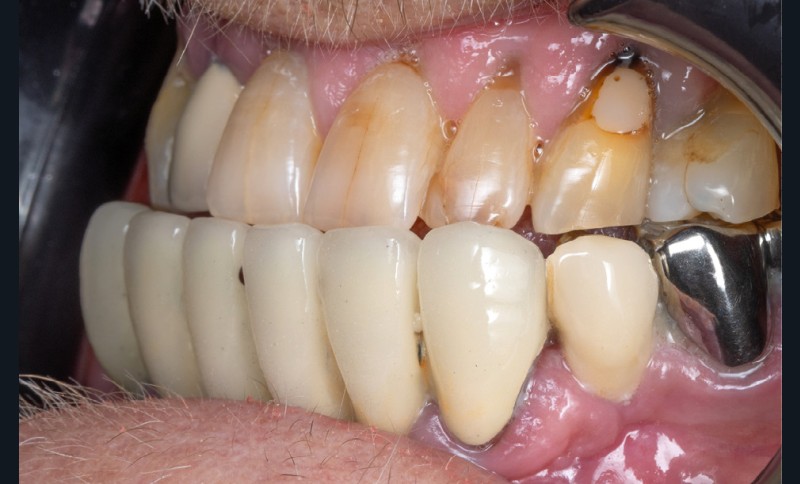

La première étape repose sur la récolte des données cliniques suivantes : – photographies exo- et endo-buccales (fig. 1), utilisées pour l’évaluation esthétique, le diagnostic initial et la communication avec le prothésiste ;